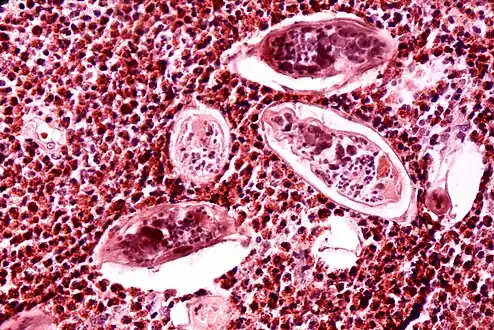

Ultrasonographic images in hepatic schistosomiasis

High-powered detailed micrograph of Schistosoma parasite eggs in human bladder tissue

S. japonicum eggs in hepatic portal tract

Identification of eggs in stools

Diagnosis of infection is confirmed by the identification of eggs in stools. Eggs of S. mansoni are about 140 by 60 µm in size and have a lateral spine. The diagnosis is improved through the use of the Kato technique, a semiquantitative stool examination technique. Other methods that can be used are enzyme-linked immunosorbent assay, circumoval precipitation test, and alkaline phosphatase immunoassay.[34]

Microscopic identification of eggs in stool or urine is the most practical method for diagnosis. Stool examination should be performed when infection with S. mansoni or S. japonicum is suspected, and urine examination should be performed if S. haematobium is suspected. Eggs can be present in the stool in infections with all Schistosoma species. The examination can be performed on a simple smear (1 to 2 mg of fecal material). Because eggs may be passed intermittently or in small numbers, their detection is enhanced by repeated examinations or concentration procedures, or both. In addition, for field surveys and investigational purposes, the egg output can be quantified by using the Kato-Katz technique (20 to 50 mg of fecal material) or the Ritchie technique. Eggs can be found in the urine in infections with S. haematobium (recommended time for collection: between noon and 3 PM) and with S. japonicum. Quantification is possible by using filtration through a nucleopore filter membrane of a standard volume of urine followed by egg counts on the membrane. Tissue biopsy (rectal biopsy for all species and biopsy of the bladder for S. haematobium) may demonstrate eggs when stool or urine examinations are negative.[35]